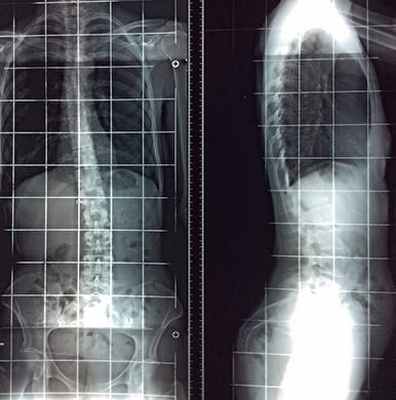

Сколиограмма или рентген всего позвоночника

Для диагностики и контроля идиопатического сколиоза необходимо увидеть весь позвоночник на одном снимке в профиль и анфас.

Сколиограмма в анфас

Сколиограмма в профиль

– Случай 17584. Заметное уменьшение искривления позвоночника после лечения по методу Filum System®. Снимок до операции 2014 года и после операции 2015 года.